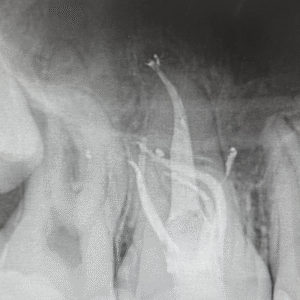

In this course, we delve into the latest endodontic techniques. As we explore the latest technologies available, we also prioritize the importance of patient communication and comfort during endodontic procedures. Our goal is to demystify the process and empower you to provide exceptional care to your patients.